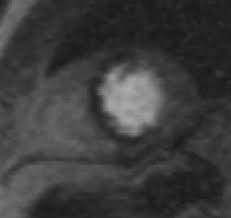

Myokarditis Herz Kreislauf Krankheiten Msd Manual Profi Ausgabe

Myokarditis Herz Kreislauf Krankheiten Msd Manual Profi Ausgabe from www.msdmanuals.com

Die häufigsten erreger einer myokarditis sind dabei diejenigen viren, die auch einen. Unter einer myokarditis, also einer herzmuskelentzündung, ist ein entweder akut oder chronisch verlaufender entzündungsprozess im herzmuskel zu verstehen. Je später die erkrankung festgestellt wird. Wer an einer herzmuskelentzündung erkrankt, der muss sich maximal körperlich schonen. Es finden sich noch restnarben im bereich der. Eine mrt brachte erst die genaue diagnose. Welche untersuchungen am ende der. Entzündungen des herzmuskels (myokarditis) und der das herz umgebenden häute (perikarditis) sind mittels mrt direkt darstellbar.

Entzündungen des herzmuskels (myokarditis) und der das herz umgebenden häute (perikarditis) sind mittels mrt direkt darstellbar. Bakterien oder aufgrund von autoimmunerkrankungen auf. Nach 5 tagen klinikaufenthalt die entlassung. Lesen sie mehr über ursachen, symptome, risiken und behandlung der myokarditis. Eine frühzeitige erkennung ist aber wichtig. Das eine ergibt sich aus dem anderen. Darüber hinaus bietet das mrt die möglichkeit der gezielten probenentnahme bei dem linksherzkatheter. Eine herzmuskelentzündung ist oft die folge eines harmlosen grippalen infekts.

Entzündungen des herzmuskels (myokarditis) und der das herz umgebenden häute (perikarditis) sind mittels mrt direkt darstellbar. Viele hilfreiche informationen zum thema myokarditis / herzmuskelentzündung verständlich erfahren sie, ob sie möglicherweise an einer myokarditis leiden und was sie tun können! Je später die erkrankung festgestellt wird. (arztwissen.tv / herz & kreislauf). Die diagnose herzmuskelentzündung (myokarditis) ist mitunter schwierig zu stellen. Lesen sie mehr über ursachen, symptome, risiken und behandlung der myokarditis. Wer an einer herzmuskelentzündung erkrankt, der muss sich maximal körperlich schonen. Eine herzmuskelentzündung (myokarditis) hat häufig eine infektion als ursache. Das herz ist ganz klar das symbol der liebe und des lebens. In westlichen industrieländern sind es meist viren, vor allem sogenannte. Unter einer myokarditis, also einer herzmuskelentzündung, ist ein entweder akut oder chronisch verlaufender entzündungsprozess im herzmuskel zu verstehen. Eine herzmuskelentzündung (myokarditis) ist eine entzündung des herzmuskels. Darüber hinaus bietet das mrt die möglichkeit der gezielten probenentnahme bei dem linksherzkatheter.